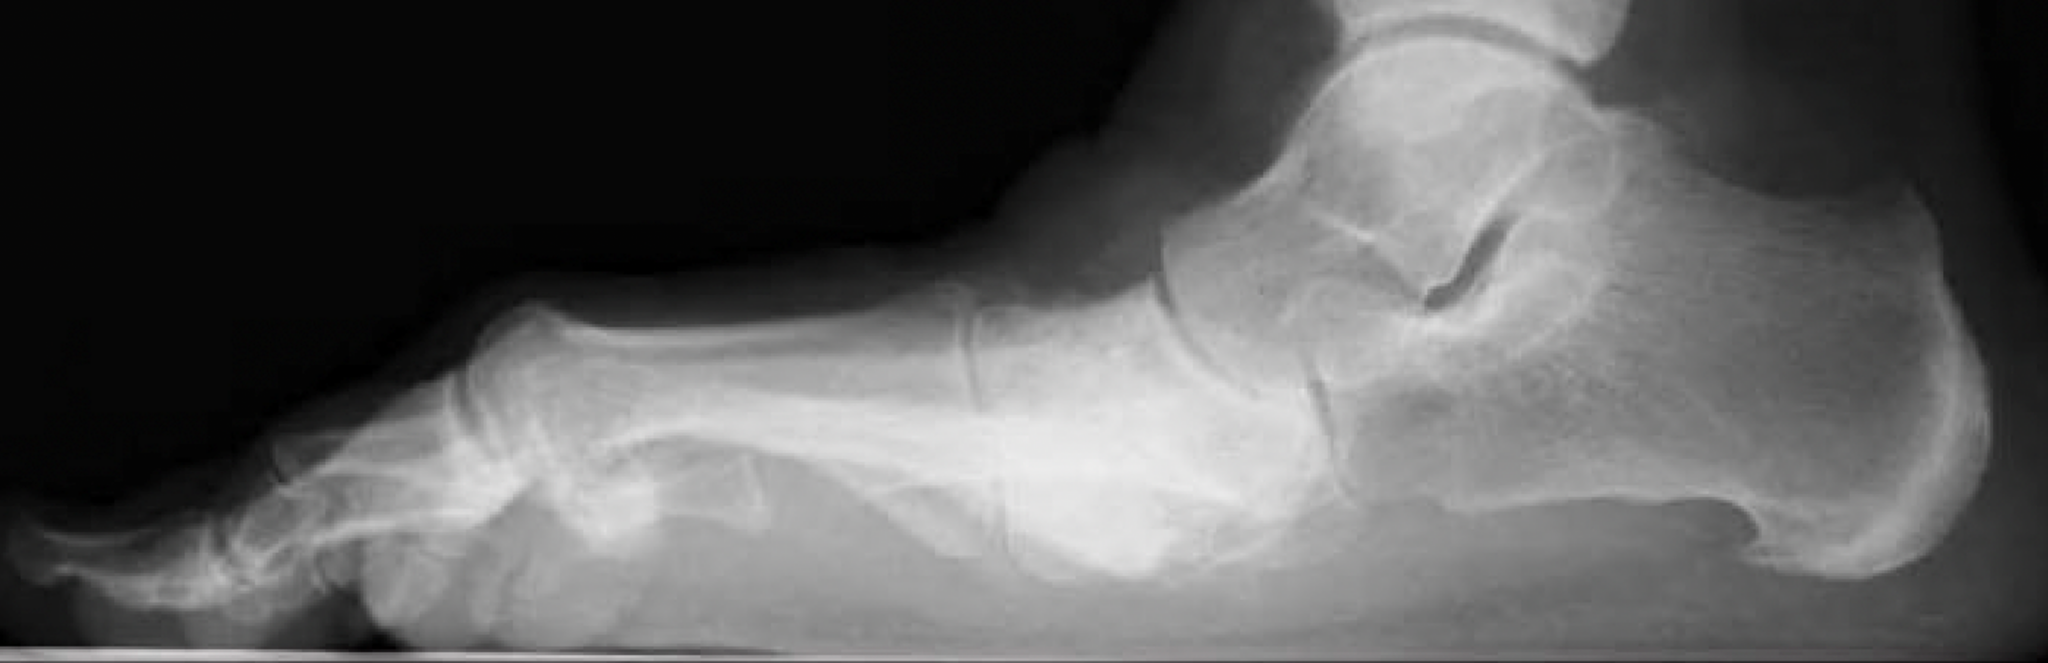

Midfoot Fusion Orthopedic Surgery for Arthritis Pain

Surgical Correction of Midfoot Arthritis With and Without Deformity Midfoot Arthritis Icd 10 Midfoot arthritis is joint inflammation that impacts the middle of the foot. Midfoot arthritis is a condition that affects the joints of the midfoot, causing pain and deformity. Midfoot arthrodesis is an effective treatment for osteoarthritis of the joint. It can cause stiffness and pain. People can develop midfoot arthritis. Identification of the affected joints is important to stipulate the.. Midfoot Arthritis Icd 10.

Case Study 12 Midfoot Arthritis Ankle, Foot and Orthotic Centre Midfoot Arthritis Icd 10 Midfoot arthrodesis is an effective treatment for osteoarthritis of the joint. Learn about the etiology, presentation, diagnosis, and treatment options, including. Identification of the affected joints is important to stipulate the. Midfoot arthritis is joint inflammation that impacts the middle of the foot. M19.072 is a billable diagnosis code used to specify a medical diagnosis of primary osteoarthritis, left ankle. Midfoot Arthritis Icd 10.

Arthritis of the midfoot Croydon Total Footcare Midfoot Arthritis Icd 10 It can cause stiffness and pain. Learn about the etiology, presentation, diagnosis, and treatment options, including. Midfoot arthritis is joint inflammation that impacts the middle of the foot. Midfoot arthrodesis is an effective treatment for osteoarthritis of the joint. Identification of the affected joints is important to stipulate the. For some, it may cause difficulty walking. People can develop midfoot. Midfoot Arthritis Icd 10.